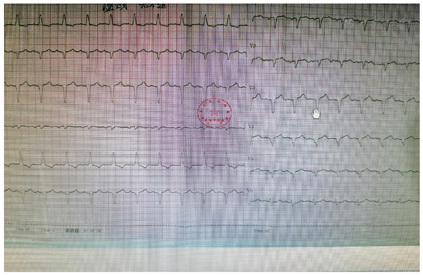

患者门诊就诊第一份心电图可见Ⅱ Ⅲ avF、V4-6导联ST段轻压低(图1);入急诊后,不适发作时可见V1-V5前壁导联T波双向、倒置,较刚入急诊第一份心电图有动态变化(图2),随后入院后心电图,不适发作和缓解时图较前变化不明显,前壁导联T波双向、倒置、低平未改善(图3,图4,图7,图5,图6,图8)。

窦性心律偶发房性早搏室性早搏部分ST-T改变

患者于我院2019年10月17日出院后规律服药,仍"间断头晕、上腹不适",遂就诊于北京友谊医院。获取一次2019年11月9日外院生化报告:血肌酐、尿素氮、总胆红素、直接胆红素,血钾、血钙、血氯、二氧化碳、渗透压、总淀粉酶、脂肪酶均正常范围,血钠132 mmol/L (137-147)、葡萄糖6.83 mmol/L (3.9-6.1)。心肌酶学显著异常:cTnI 8.552 ng/mL(0-0.03),CK 632.4 U/L (<310),CK-MB 125.4 ng/mL(0-6.0),乳酸脱氢酶371 U/L (127-250)。并因"病情恶化"转入重症监护室治疗,获取一份心电图如下(图17),为:窦性心动过速,广泛前壁、下壁导联已呈QS型,较我院出院前心电图有显著变化。外院具体治疗不详。